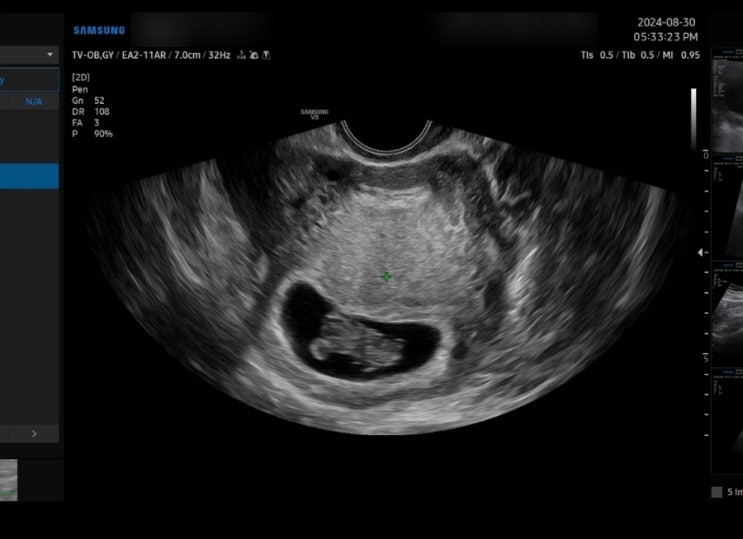

임신 9주 차 젤리 곰 확인 배 초음파, 질 초음파 비교, 혈전 예방 아스피린 처방, 태아보험 산모 특약 / 큐트루

안녕하세요 큐트루예요. 임신 9주 차 젤리 곰 확인 배 초음파, 질 초음파 비교, 혈전 예방 아스피린 처방, ...